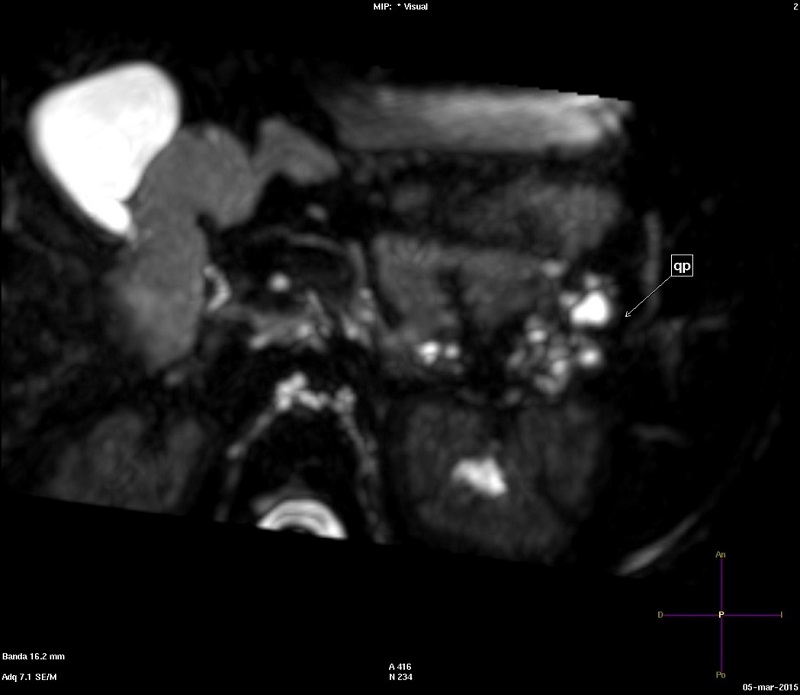

Niña de cinco años con un síndrome polimalfortativo consistente en médula anclada intervenida, quistes renales, polidactilia y retraso psicomotor, con diagnóstico genético de cromosomopatía por duplicación 13q31.1-q33.2 y deleción 13qter. La niña fue derivada a consultas externas de Digestivo por el hallazgo casual de quistes pancreáticos. Los quistes pancreáticos fueron objetivados por primera vez en ecografía abdominal a los dos años de vida como parte del estudio del cuadro polimalformativo, hallándose un páncreas ligeramente aumentado de tamaño, así como múltiples quistes a nivel de la cola y el cuerpo de alrededor de 10 mm. La paciente se encontraba asintomática desde el punto de vista gastrointestinal. Normalidad analítica, incluyendo amilasa y lipasa. Se realizaron controles ecográficos seriados, así como una resonancia magnética a los cinco años, en la que se observó disminución del tamaño de los quistes, siendo el mayor de ellos de 3 mm y limitándose a la cola pancreática (Fig. 1). Se decidió mantener actitud expectante, dado su carácter asintomático y el tamaño pequeño de los mismos.

| Figura 1. Resonancia magnética en plano axial con secuencia colangiográfica potenciada en T2, en la que se reconocen múltiples quistes hiperintensos en la cola pancreática (marcado con una flecha, y rotulado como "qp") |